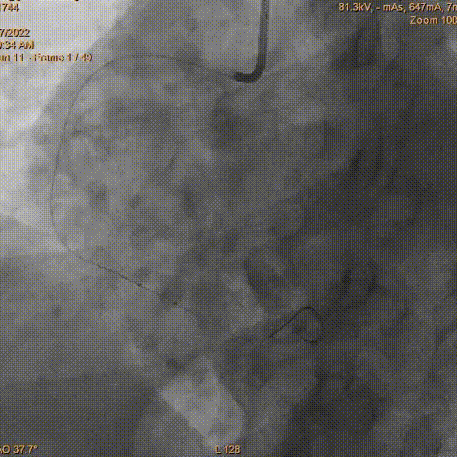

冠脉造影

LCA大致正常

RCA迂曲远段中重度狭窄